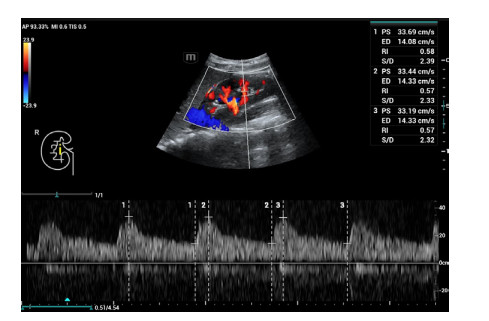

肾脏超声检查方法:所有超声检查在患者入住ICU当天由同一位超声诊断医生完成;患者取平卧位,将SC6-1s探头置于右腰部腋后线附近横切发现肾脏,再行肾脏冠状切面扫查,清晰显示上、下两极轮廓及肾内结构后启用彩色多普勒功能键显示肾脏血管并应用频谱多普勒分别于肾髓质与肾柱间检测叶间动脉(图 1)、肾窦内检测段动脉(图 2)、肾门处检测主动脉(图 3),选择3个相似且完整的频谱测量其阻力指数(resistance index, RI)值并取平均。多普勒超声检查时,声束与血流夹角尽量小于20°,取样容积在2~4 mm之间。

| 图 2 右肾段动脉RI值 Fig 2 The resistance index (RI) of the right renal segment artery |